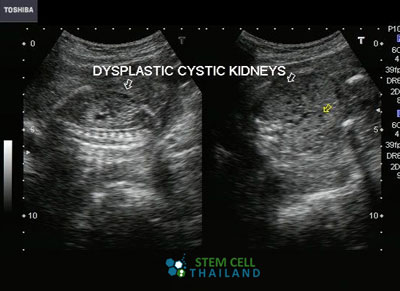

Polycystic kidney disease “PKD” is a medical condition wherein numerous fluid-filled cysts are found to have grown in either or both kidneys. These cysts cause enlargement and, if left untreated, can grow to an abnormal size that can destroy normal kidney structure and affect kidney function that could lead to eventual kidney failure and death

The cysts are mostly benign or non-carcinogenic, as most of them are full of bodily fluids or water. However, their sizes could grow larger than the kidney itself because of continual fluid accumulation.